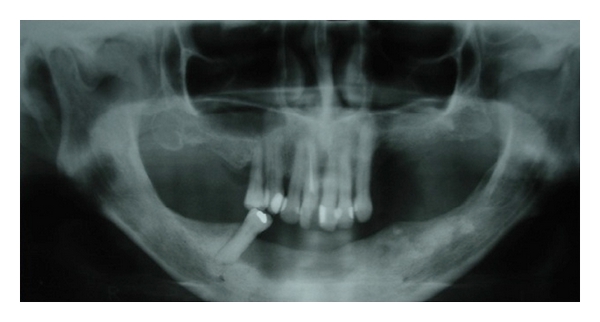

Case 1. A 77-year-old white female was seen at the Oral Medicine Clinic of the Federal University of Alfenas (UNIFAL-MG) with an asymptomatic, smooth surfaced, normal colored tumor on the anterior mandibular alveolar ridge, with two months evolution. A drainage point with purulent material was also present (Figure 1(a)). The patient’s medical history was unremarkable and no changes were noted on extraoral examination. Radiographic examination revealed osteolysis and bone sequestration on the mandibular alveolar ridge (Figure 1(b)). Based on clinical and radiographic findings, a provisional diagnosis of osteomyelitis was rendered. The patient was given amoxicillin (500 mg, three times/day) for 15 days and subsequently underwent excision of the bone sequestrum and curettage of the granulation tissue (Figure 2). The material was submitted to histopathological examination which revealed nonviable bone and a mixed inflammatory infiltrate of lymphocytes and plasma cells, confirming the diagnosis of chronic suppurative osteomyelitis. The area healed appropriately within one month (Figures 3(a) and 3(b)). The patient has been under follow-up for 5 years with no signs of recurrence.

(a)

(b)